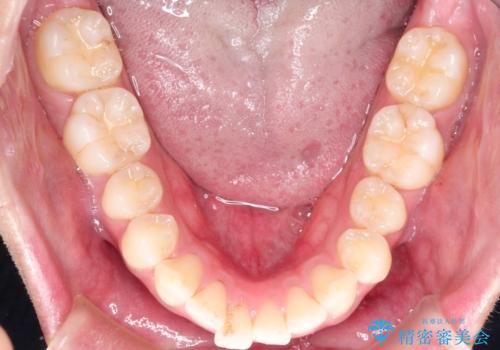

前歯の隙間を閉じたい 口元も下げたい ハーフリンガルによる抜歯矯正

- 矯正装置

- ハーフリンガル

上下左右の歯を1本ずつ抜歯しして、上顎の前歯を後方に移動させるのと、正中の隙間を閉じる計画としました。

装置はなるべく目立たないものをご希望でしたので、ハーフリンガルを選択されました。